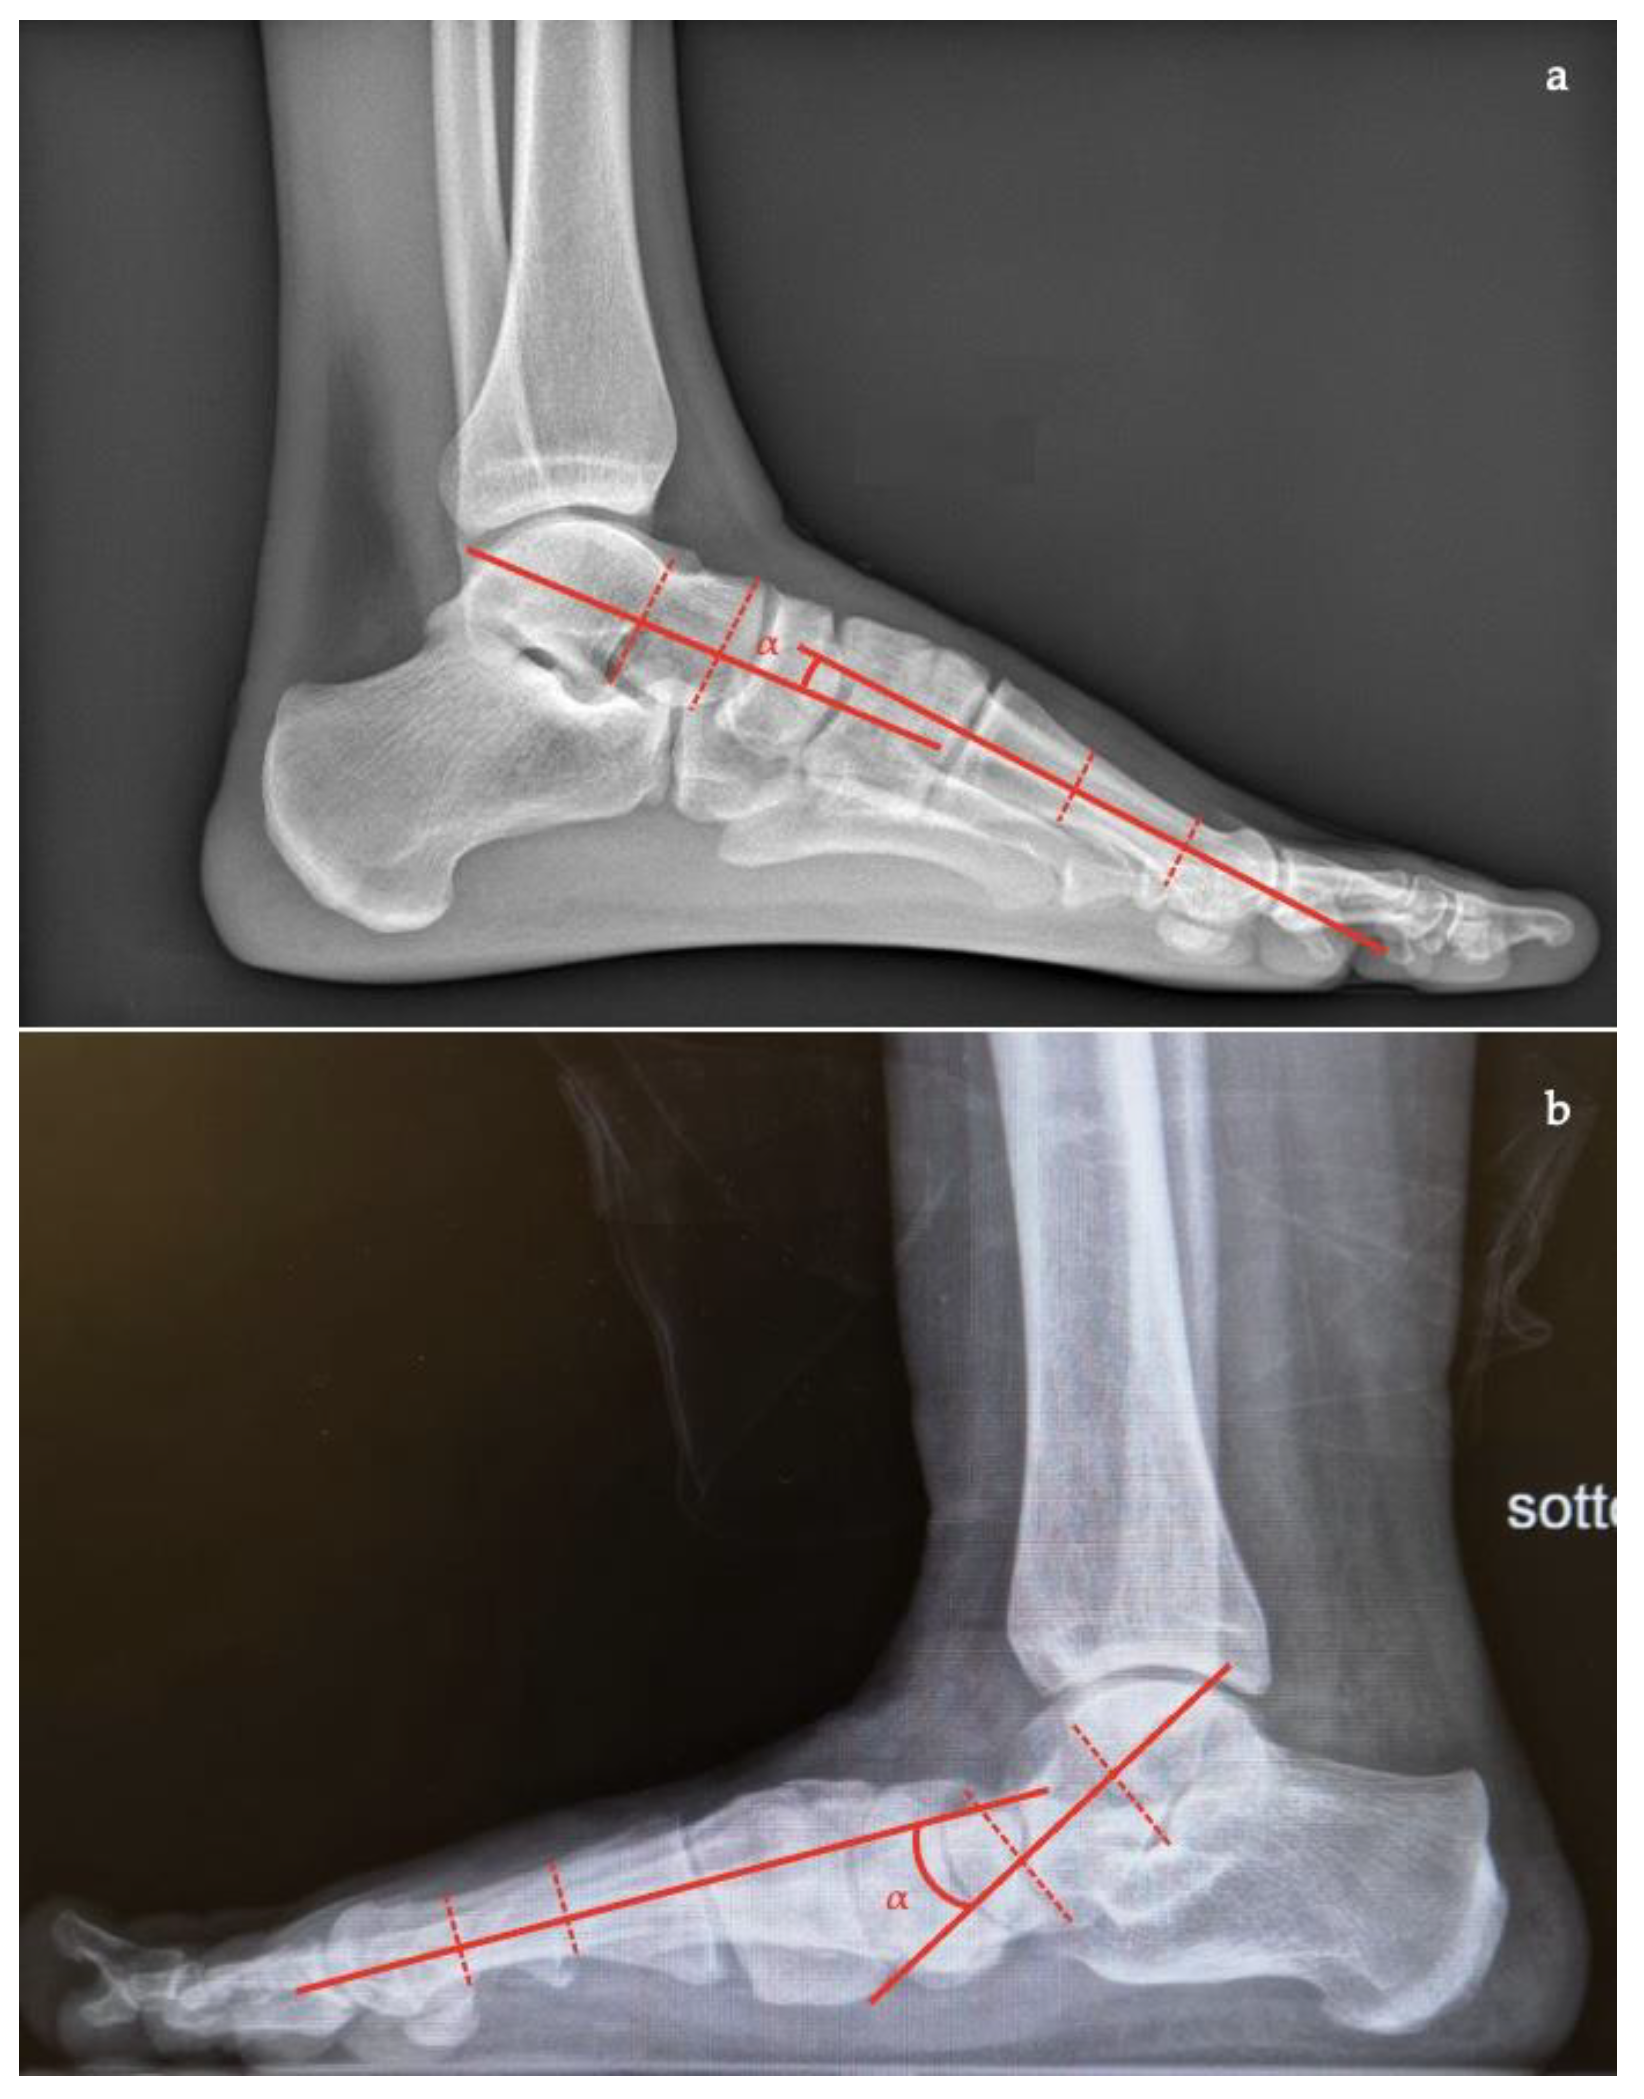

- Talar–first metatarsal angle (Meary’s angle), the normal value is 0 ± 10 degrees and is increased in flatfoot deformity (often >20°, apex directed plantarly) (Figure 5);

- Calcaneal pitch, the angle between the line parallel to the ground and the line along the inferior inclination axis of the calcaneus (normal, 20–30°; flatfoot, <20°) (Figure 6);